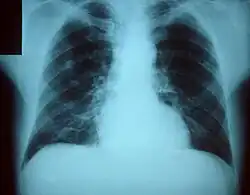

La excepción a esta norma la encontramos en la tuberculosis, considerada por varios autores como la enfermedad más antigua conocida en el hombre. Una de las hipótesis más aceptadas sobre el surgimiento del Mycobacterium (el germen causante de esta enfermedad) propone que el antepasado común denominado M. archaicum habría dado origen a los modernos Mycobacterium, incluido el M. tuberculosis.[2] La mutación se habría producido durante el Neolítico, en relación con la domesticación de bóvidos salvajes en África. Las primeras evidencias de tuberculosis en humanos se han encontrado en restos óseos del Neolítico, en un cementerio próximo a Heidelberg, supuestamente pertenecientes a un adulto joven, y datados en torno a cinco mil años antes de nuestra era.[3] También se han encontrado datos sugestivos de tuberculosis en momias egipcias datadas entre los años 3000 y 2400 a. C.[4]